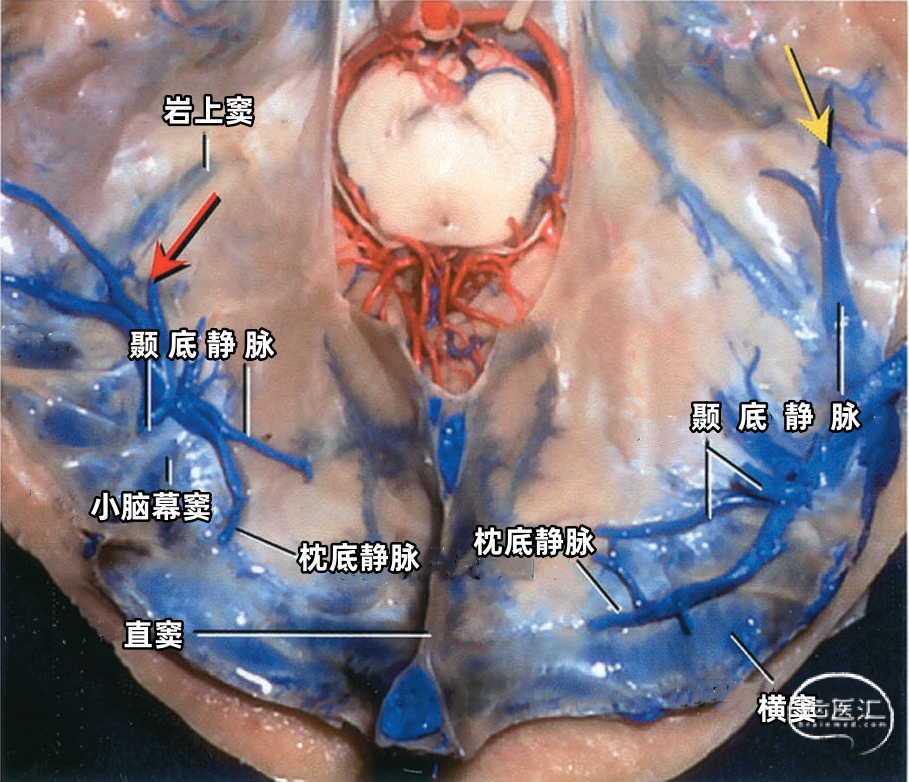

每侧小脑幕有两个恒定但不对称的静脉窦,即内侧小脑幕窦和外侧小脑幕窦。 内侧小脑幕窦由小脑上表面的回流静脉汇聚而成。内侧小脑幕窦向内侧引流入直窦,或直窦与横窦的汇合处。 外侧小脑幕窦由颞叶和枕叶基底面和外侧面的回流静脉汇聚而成。外侧小脑幕窦起自小脑幕的外侧部分,并向外侧引流入横窦的末端。 下图示抬起小脑幕,可见来自小脑、在小脑幕下缘入窦的桥静脉。左侧黄色箭头显示一支较大的静脉自小脑上表面进入内侧小脑幕窦。右侧红色箭头显示一支粗大的来自小脑上表面的桥静脉在窦汇前方进入内侧小脑幕窦。

下图示切除左侧的小脑幕。黄色箭头示进入上图黄色箭头所示的小脑幕窦的小脑桥静脉。

下图示汇入外侧小脑幕窦的颞底静脉、枕底静脉。左侧红色箭头指示左侧汇入小脑幕窦属支的颞底长静脉。颞底静脉汇入有多个属支的小脑幕窦。右侧黄色箭头显示汇入右侧小脑幕窦的静脉属支。 下图示(左侧)颞底静脉和枕底静脉汇聚于两个横窦内侧的短小脑幕窦。(右侧)Labbé静脉和颞后静脉直接引流入横窦。左侧小脑幕的另一个窦(小脑幕内侧窦)(黄色箭头)接受来自小脑的引流,向内侧经过小脑幕汇入窦汇。

下图示小脑幕的上面观。右侧Labbé静脉和颞后静脉直接引流入横窦。

小脑幕组(上图 绿色)的桥静脉汇入行经小脑幕的静脉窦,即小脑幕窦或小脑幕附近的横窦和岩上窦。本组静脉引流颞叶外侧面和底面、枕叶的底面,包括颞底静脉、枕底静脉和来自颞叶外侧面的降静脉,如Labbé静脉。 除Labbé静脉外,这些静脉虽然有可能进入横窦,但大多数围绕半球的下缘汇聚于枕前切迹到达外侧小脑幕窦。而Labbé静脉通常汇入横窦。大脑底面的桥静脉汇入静脉窦之前,经常粘连于与中颅窝底硬膜和小脑幕表面。 从外侧面引流入小脑幕窦的静脉包括颞前静脉、颞中静脉、颞后静脉和Labbé静脉。

从下表面引流入小脑幕窦的静脉包括颞底前静脉,颞底中静脉、颞底后静脉和枕底静脉。 内侧小脑幕窦接受来自小脑的静脉血流,并加入直窦。基底窦位于斜坡。 大脑镰组(上图 紫色)由直接或经由大脑内静脉、基底静脉和大脑大静脉汇入下矢状窦或直窦的静脉构成。汇入直窦的静脉(上图 紫色)或其属支,引流胼胝体附近部分的额叶、顶叶和颞叶内侧部,此组静脉的引流区域大致相当于大脑边缘叶,包括终板旁静脉,额眶后静脉、嗅静脉、胼周前静脉、胼周后静脉,钩回静脉、海马前静脉、颞内侧静脉和距状前静脉。